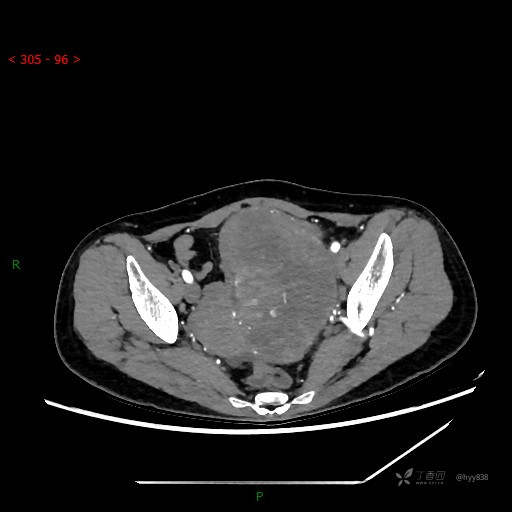

增强动脉期